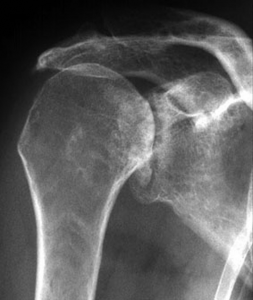

Der klassische Verschleiß des Schultergelenkes tritt im Vergleich zum Hüft- und Kniegelenk beim älteren Menschen seltener auf. Hierbei erfolgen eine Zerstörung des Gelenkknorpels und die Deformierung der Gelenkflächen, die zu einer schmerzhaften Bewegungseinschränkung des Schultergelenkes führen (Abb. 34, 37).